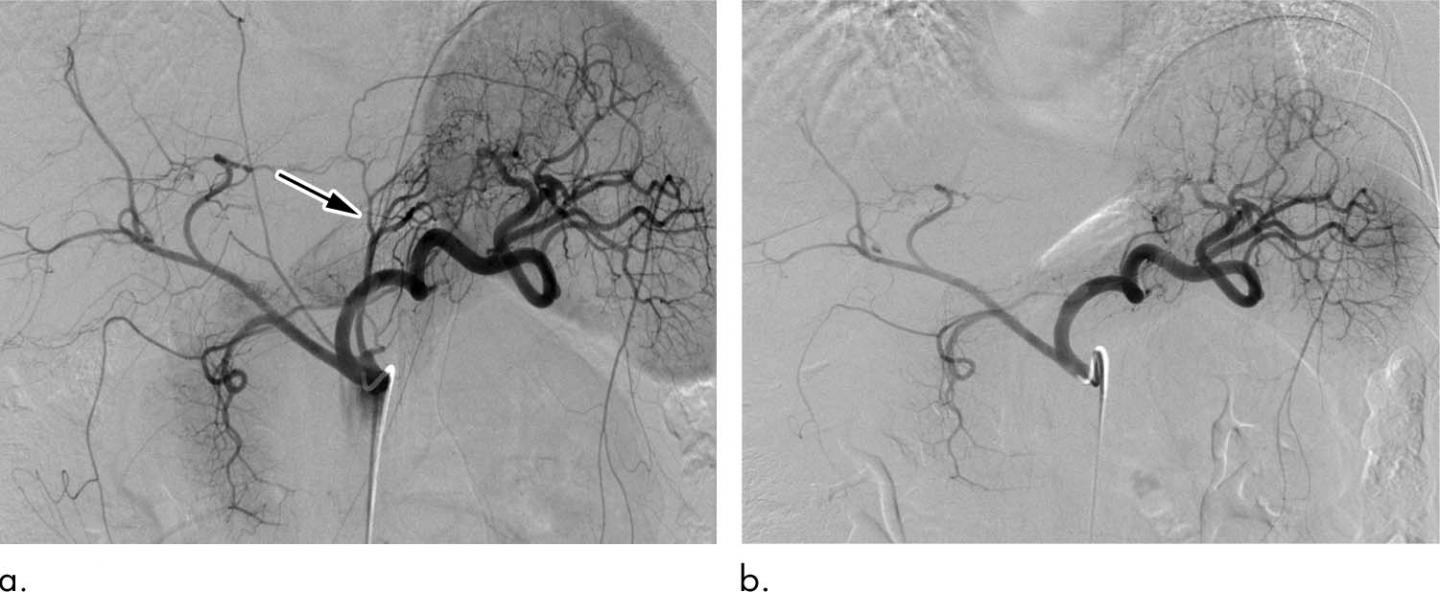

Bariatric embolization has emerged in recent years as one such option. In the procedure, microscopic spheres are introduced through a catheter into the arteries that supply blood to the stomach. The blocking of the arteries with the beads produces a reduction in blood flow--enough to suppress production of hunger-stimulating hormones but not enough to cause tissue damage.